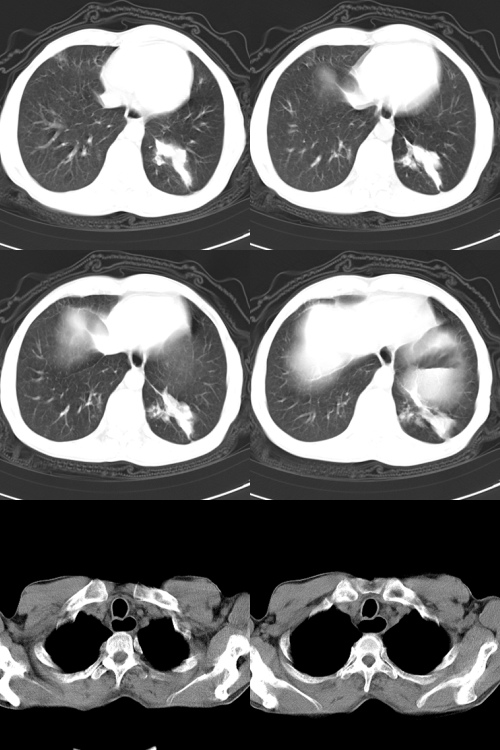

以下是引用zsl6918在2009-2-7 7:38:00的发言:[br]恶性度极高的肺癌,肺门及纵隔淋巴结转移。

以下是引用余辉在2009-2-7 8:29:00的发言:[br]考虑左下肺周围型肺癌伴肺门、纵隔淋巴转移及右肺转移